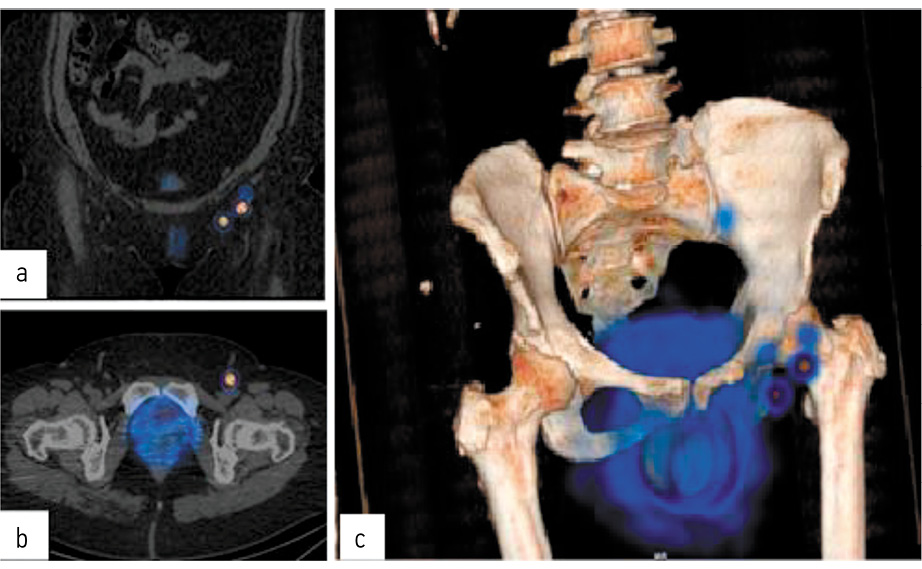

Через 2 ч после введения РФП выполнена ОФЭКТ/КТ таза (рис. 11).

Рис. 11. ОФЭКТ/КТ таза пациентки А. во фронтальной (a), аксиальной (b) проекциях и 3D-реконструкция (c).

В условиях операционной γ-детектором произведен поиск СЛУ в паховых областях с обеих сторон. В паховой области слева определена точка активности до 329 имп/с (рис. 12).